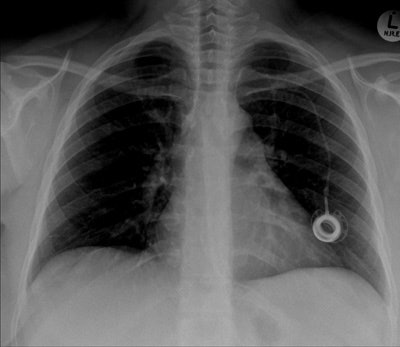

The portacath fracture was incidentally discovered on chest radiograph, which showed cardiac migration of the proximal fragment. Echocardiography was performed and showed preserved left ventricular function with ejection fraction of about 50% to 55%. No regional wall motion abnormalities seen. Linear shadow was seen on echocardiography, representing the retained fragment.

The postoperative radiograph showed no residual fragments.